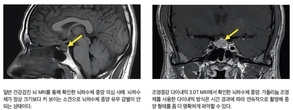

• [이런 병, 저런 병] <45>비염·축농증으로 오인, 무서운 ‘비부비동암’

• <건강칼럼> 흔한 질환이지만 일반인은 잘 모르는 뇌하수체 종양